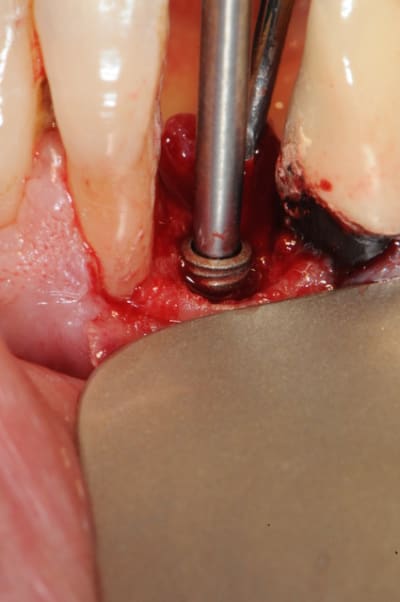

1) foret unique

2) taraudage (fortement recommandé)

3)4) packaging

5) vis de couverture transgingivale en pick

6) porte implant manuel

7)8) on met l'implant avec ses petits didis

9)10)11) implant in situ